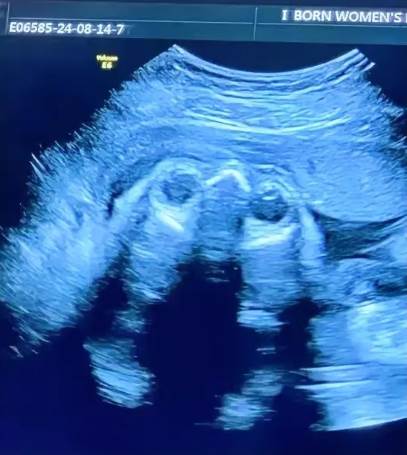

其實醫生早該告訴她:四維彩超里蜷縮的小腳只有葡萄大,握拳的樣子像在說「媽媽我來了」。那些執著了半輩子的「男女」,在孩子第一次睜眼望向你時,突然就變得不重要了。孩子健康才是寶,珍惜這份緣!對兒女有分別心,是心的問題,其實兒女都是你的種。